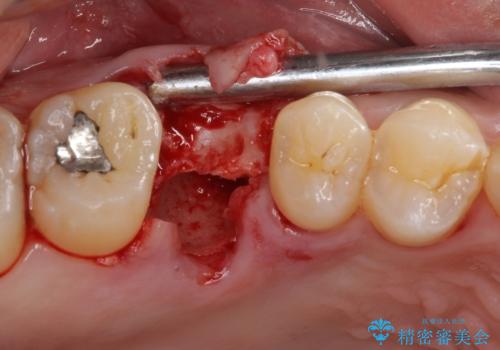

インプラント処置は、抜歯即時埋入を行い、十分な安定性が確認できたため、当日仮歯を装着しました。

インプラントが生着するのを待っている間に反対側の根管治療を行い、左右同時に補綴治療を行いました。